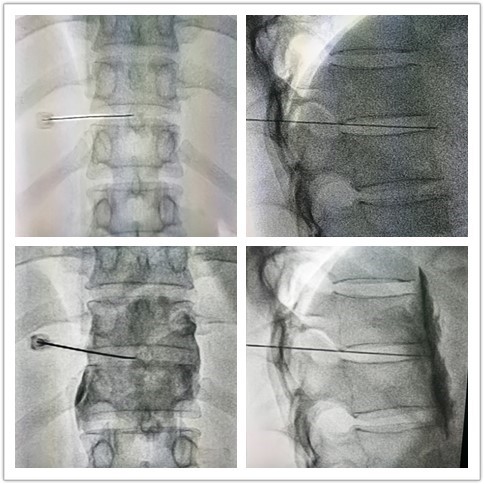

1989 C CT